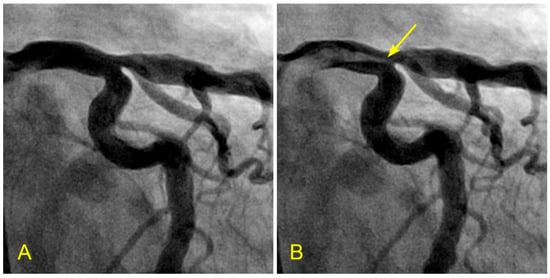

Figure 1.

The left anterior descending artery (LAD) in the anterior–posterior cranial view. There is a narrowing in the mid-segment of the LAD, distal to the origin of a moderate-size diagonal (arrow). The current angiography technique only shows the degree of stenosis without critical information on how the lesion was formed and how it will progress in the near or far future.